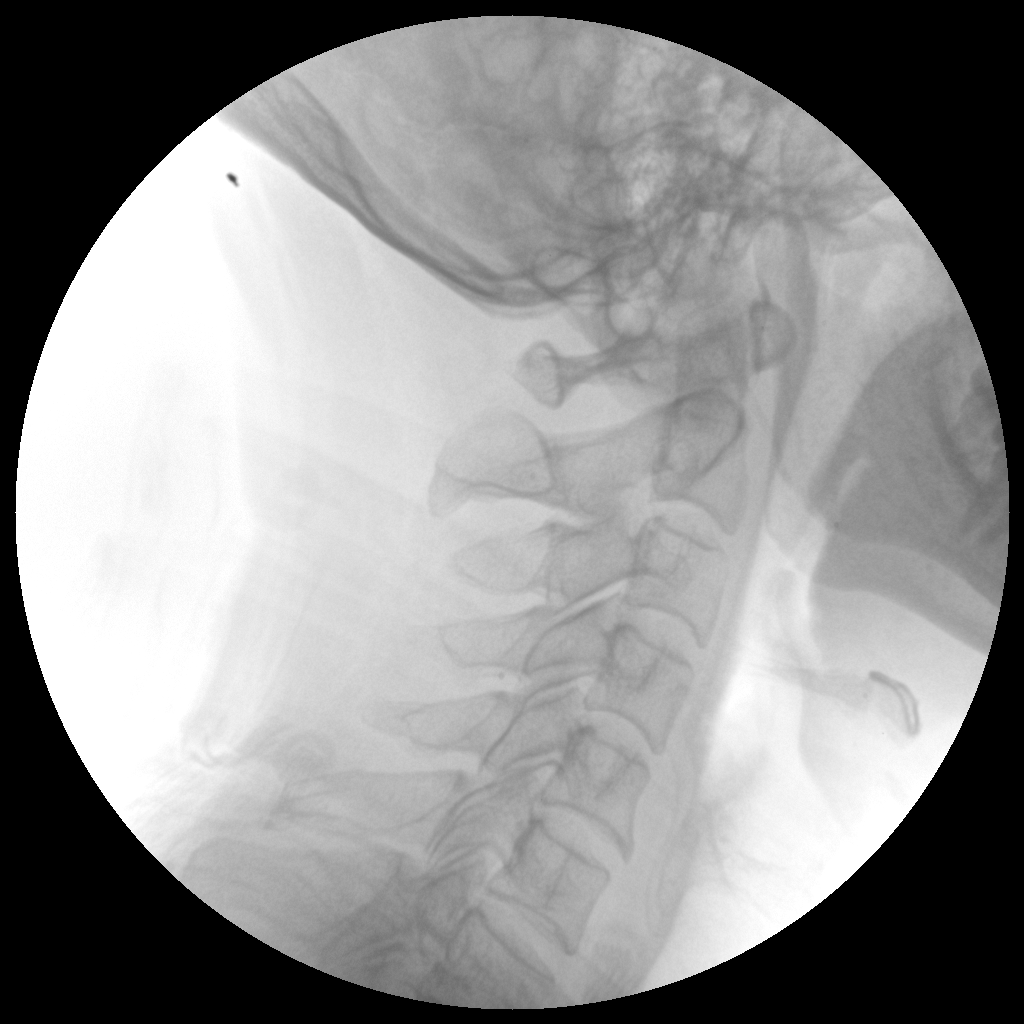

PLX112C 系列高频移动式手术X射线机

手术导航定位系统

●经典图文工作站,搭配双监双控,操作更自如●全数字化百万像素影像系统,图像清晰●独特的电动辅助支撑臂设计, 临床操作轻松自如●具备多种工作模式,满足更多临床需求●人体图形化触摸屏设计,操作方便快捷